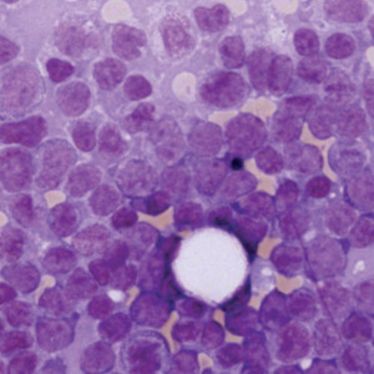

Vortrag Professor Dr. med. Martin Dreyling

Vortrag Professor Dr. med. Martin Dreyling

14.04.2015

Vortrag Professor Dr. med. Ulrich Dührsen

Vortrag Professor Dr. med. Ulrich Dührsen